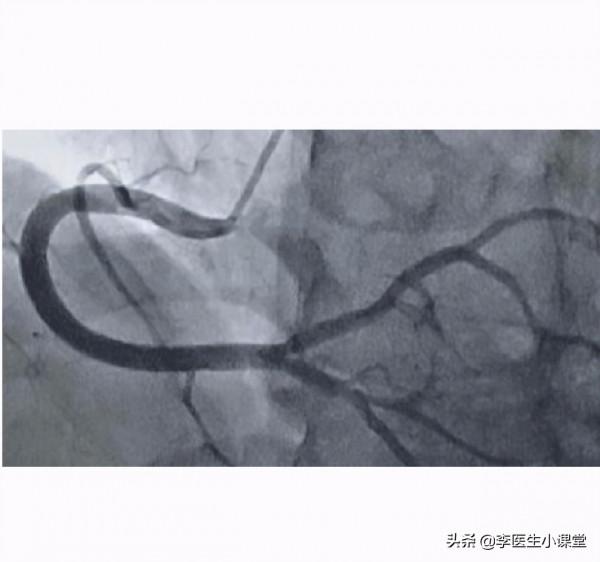

然而這次醫生診斷出來的結果就沒有第一次那麼明朗了,第一次診斷的時候陳先生冠脈造影顯示左前降支狹窄50--60%,右冠狀動脈中段狹窄40%,完全是屬於不用安裝心臟支架的程度;然而第二次就診,由於陳先生的斷續服藥,冠脈造影顯示他原本就狹窄的左前降支那一段堵了85%,遠端也有著不同程度的狹窄,迴旋支狹窄50%,如下圖冠脈造影所示,醫生建議陳先生植入心臟支架。

血管狹窄的冠脈造影